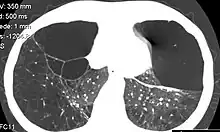

CT scan of the lung showing bullae in the lower lung lobes of a subject with type alpha-1-antitrypsin deficiency. There is also increased lung density in areas with compression of lung tissue by the bullae.

• A bulla has a wall thickness of less than 1 mm.[2] By radiology definition, it has a total size of greater than 1 cm.[3] By pathology definition, it originates in the lung parenchyma (rather than in the pleurae).[4]